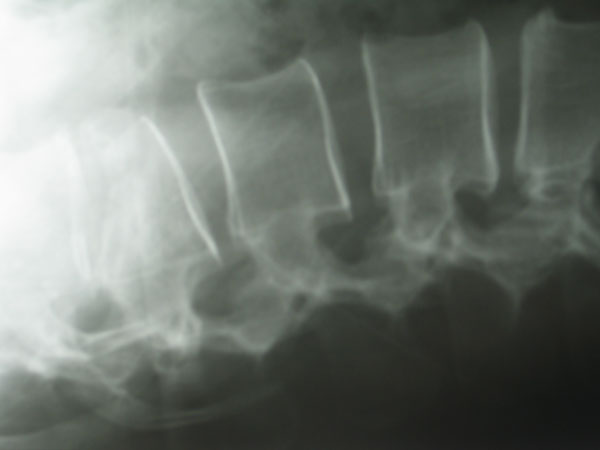

Kyphoplastie

Bei der Kyphoplastie handelt es sich um eine Variante der Vertebroplastie. Genau wie bei der konventionellen Vertebroplastie werden unter Computertomographischer bzw. Röntgenbildwandlerkontrolle ohne Hautschnitt über einen minimalinvasiven Zugang zwei Kanülen transpedikulär (durch die Wirbelbogenwurzel, s.o.) eingebracht. Über die Kanülen werden zwei Arbeitskanülen eingebracht, über diese werden wiederum zwei mit Röntgenkontrastmittel „aufblasbare“ Ballons in den gebrochenen Wirbel eingeführt. Diese Ballons werden nunmehr unter Röntgenkontrolle und elektronischer Druckkontrolle vorsichtig aufgeblasen. Hierunter kommt es idealerweise zu einer nahezu vollständigen Wiederherstellung der ursprünglichen Wirblkörperkontur. Hiernach wird das Kontrastmittel aus den Ballons abgelassen, die zusammengefallenen Ballons können über die Arbeitskanüle entfernt werden. In den nunmehr im gebrochenen Wirbel gewonnenen Hohlraum wird dann über weitere spezielle Kanülen der vorbereitete Knochenzement ohne Druck eingespritzt.

Schematische Darstellung der Kyphoplastie

Der Vorteil der Kyphoplastie besteht darin, daß der Knochenzement durch das Schaffen eines Hohlraumes ohne großen Druck eingespritzt werden kann, dieses soll bis zu einem gewissen Grad einen Zementaustritt aus dem Wirbelkörper z.B. in den Wirbelkanal verhindern. Anmerkend hierzu muß gesagt werden, das ein Zementaustritt aus dem Wirbel bedeutungslos ist, selbst das Eintreten von geringen Mengen Zement in den Wirbelkanal verläuft völlig asymptomatisch. Das Eintreten einer Zementembolie soll ebenfalls durch die geringe Druckaufwendung während des Einspritzprozesses vermindert werden. Mit der Kyphoplastie hat der Wirbelsäulenchirurg bis zu einem gewissen Grade die Möglichkeit, eine Wiederaufrichtung des gebrochenen Wirbels zu erreichen. Diese Möglichkeit ergibt sich bei der konventionellen Vertebroplastie nur sehr beschränkt, hier kann eventuell in Narkose bei frischen Frakturen durch entsprechende Lagerungsmöglichkeiten eine teilweise Wiederaufrichtung des Wirbels erreicht werden. Der Nachteil der Kyphoplastie ist in dem deutlich höheren Preis des Verfahrens zu sehen. Minimalinvasive Verfahren